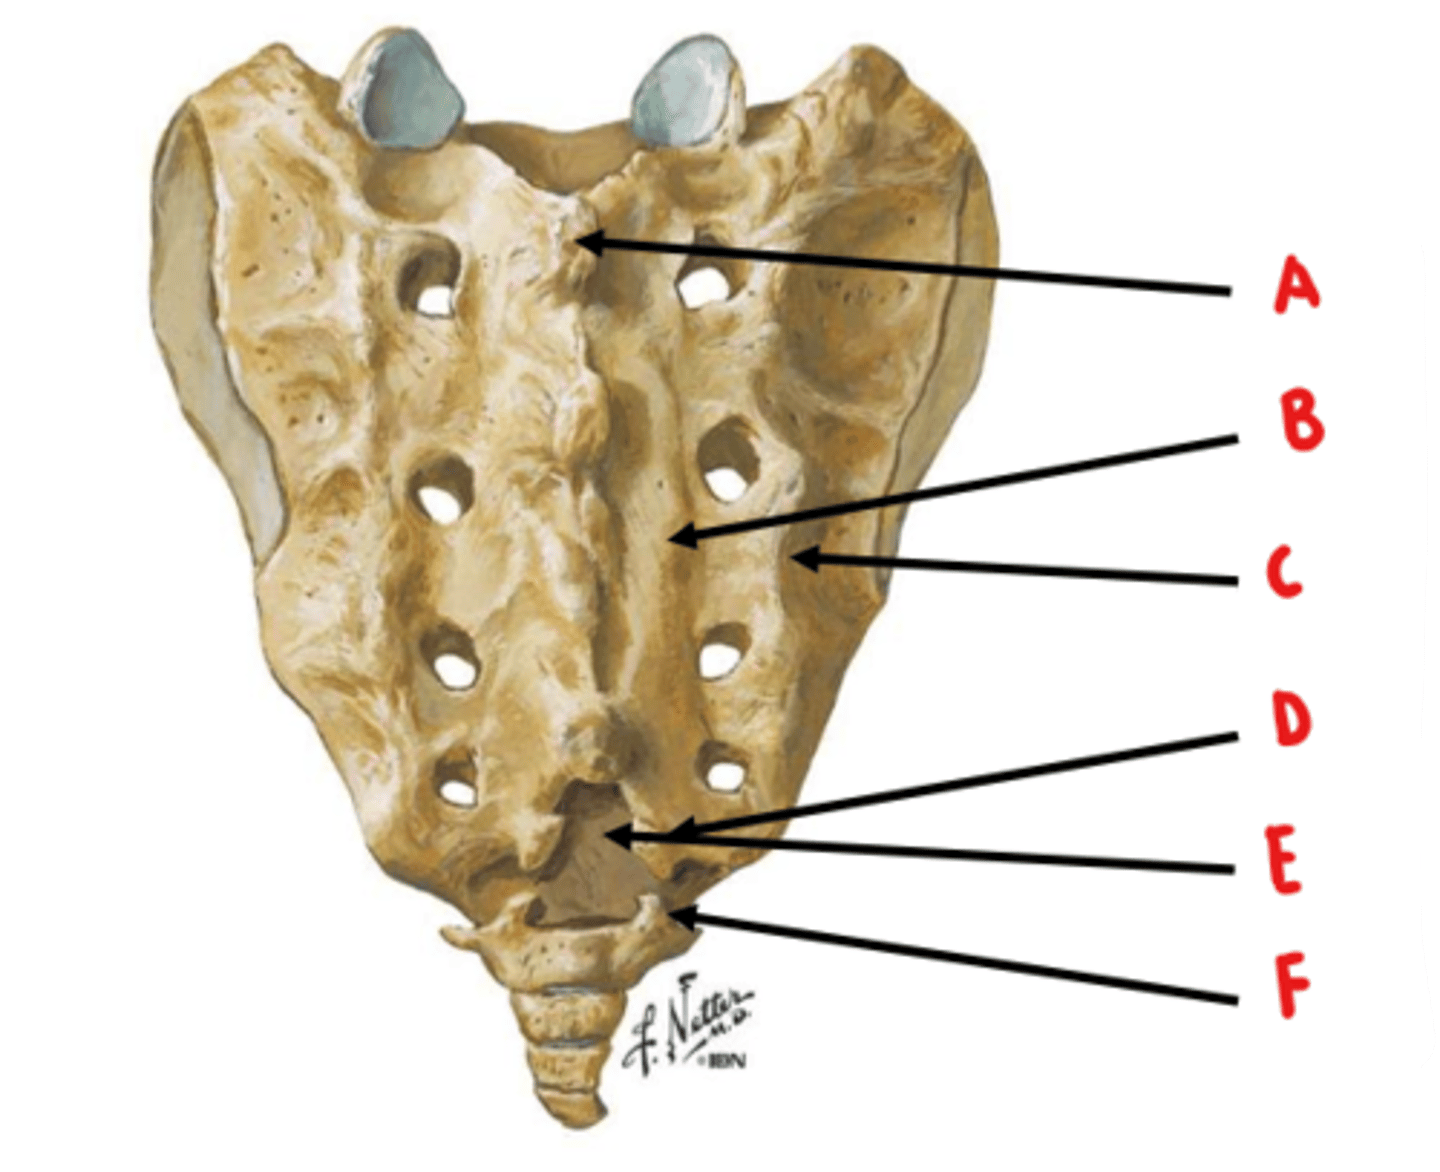

median sacral crest

Identify A

medial sacral crest

Identify B

lateral sacral crest

Identify C

sacral cornua

Identify D

sacral hiatus

Identify E

coccygeal cornua

Identify F

anterior sacral foramen = ventral rami

posterior sacral foramen = dorsal rami

ventral rami are larger because they innervate a larger area of tissue

What structures exit through the anterior and posterior sacral foramen? Which is larger and why?